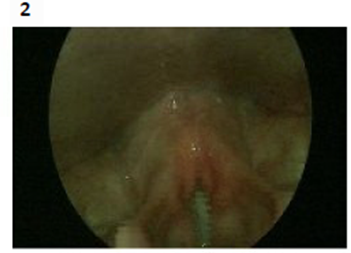

Endoscopic vocal cord examination pictures (one year after the injury) as shown down:

Lt vocal cord weakness with thickening post augmentation. Figures